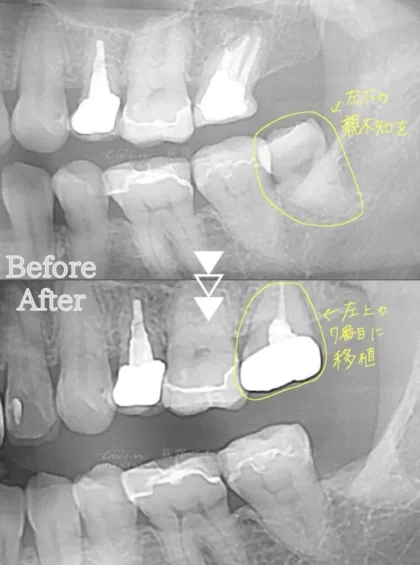

実際の症例紹介

こちらの患者様は左上の歯に違和感があり診査・診断を受けた結果、左下の親知らずを使用して移植することになりました。

自分の歯が活用できると、安心感が高まりますよね⤴️